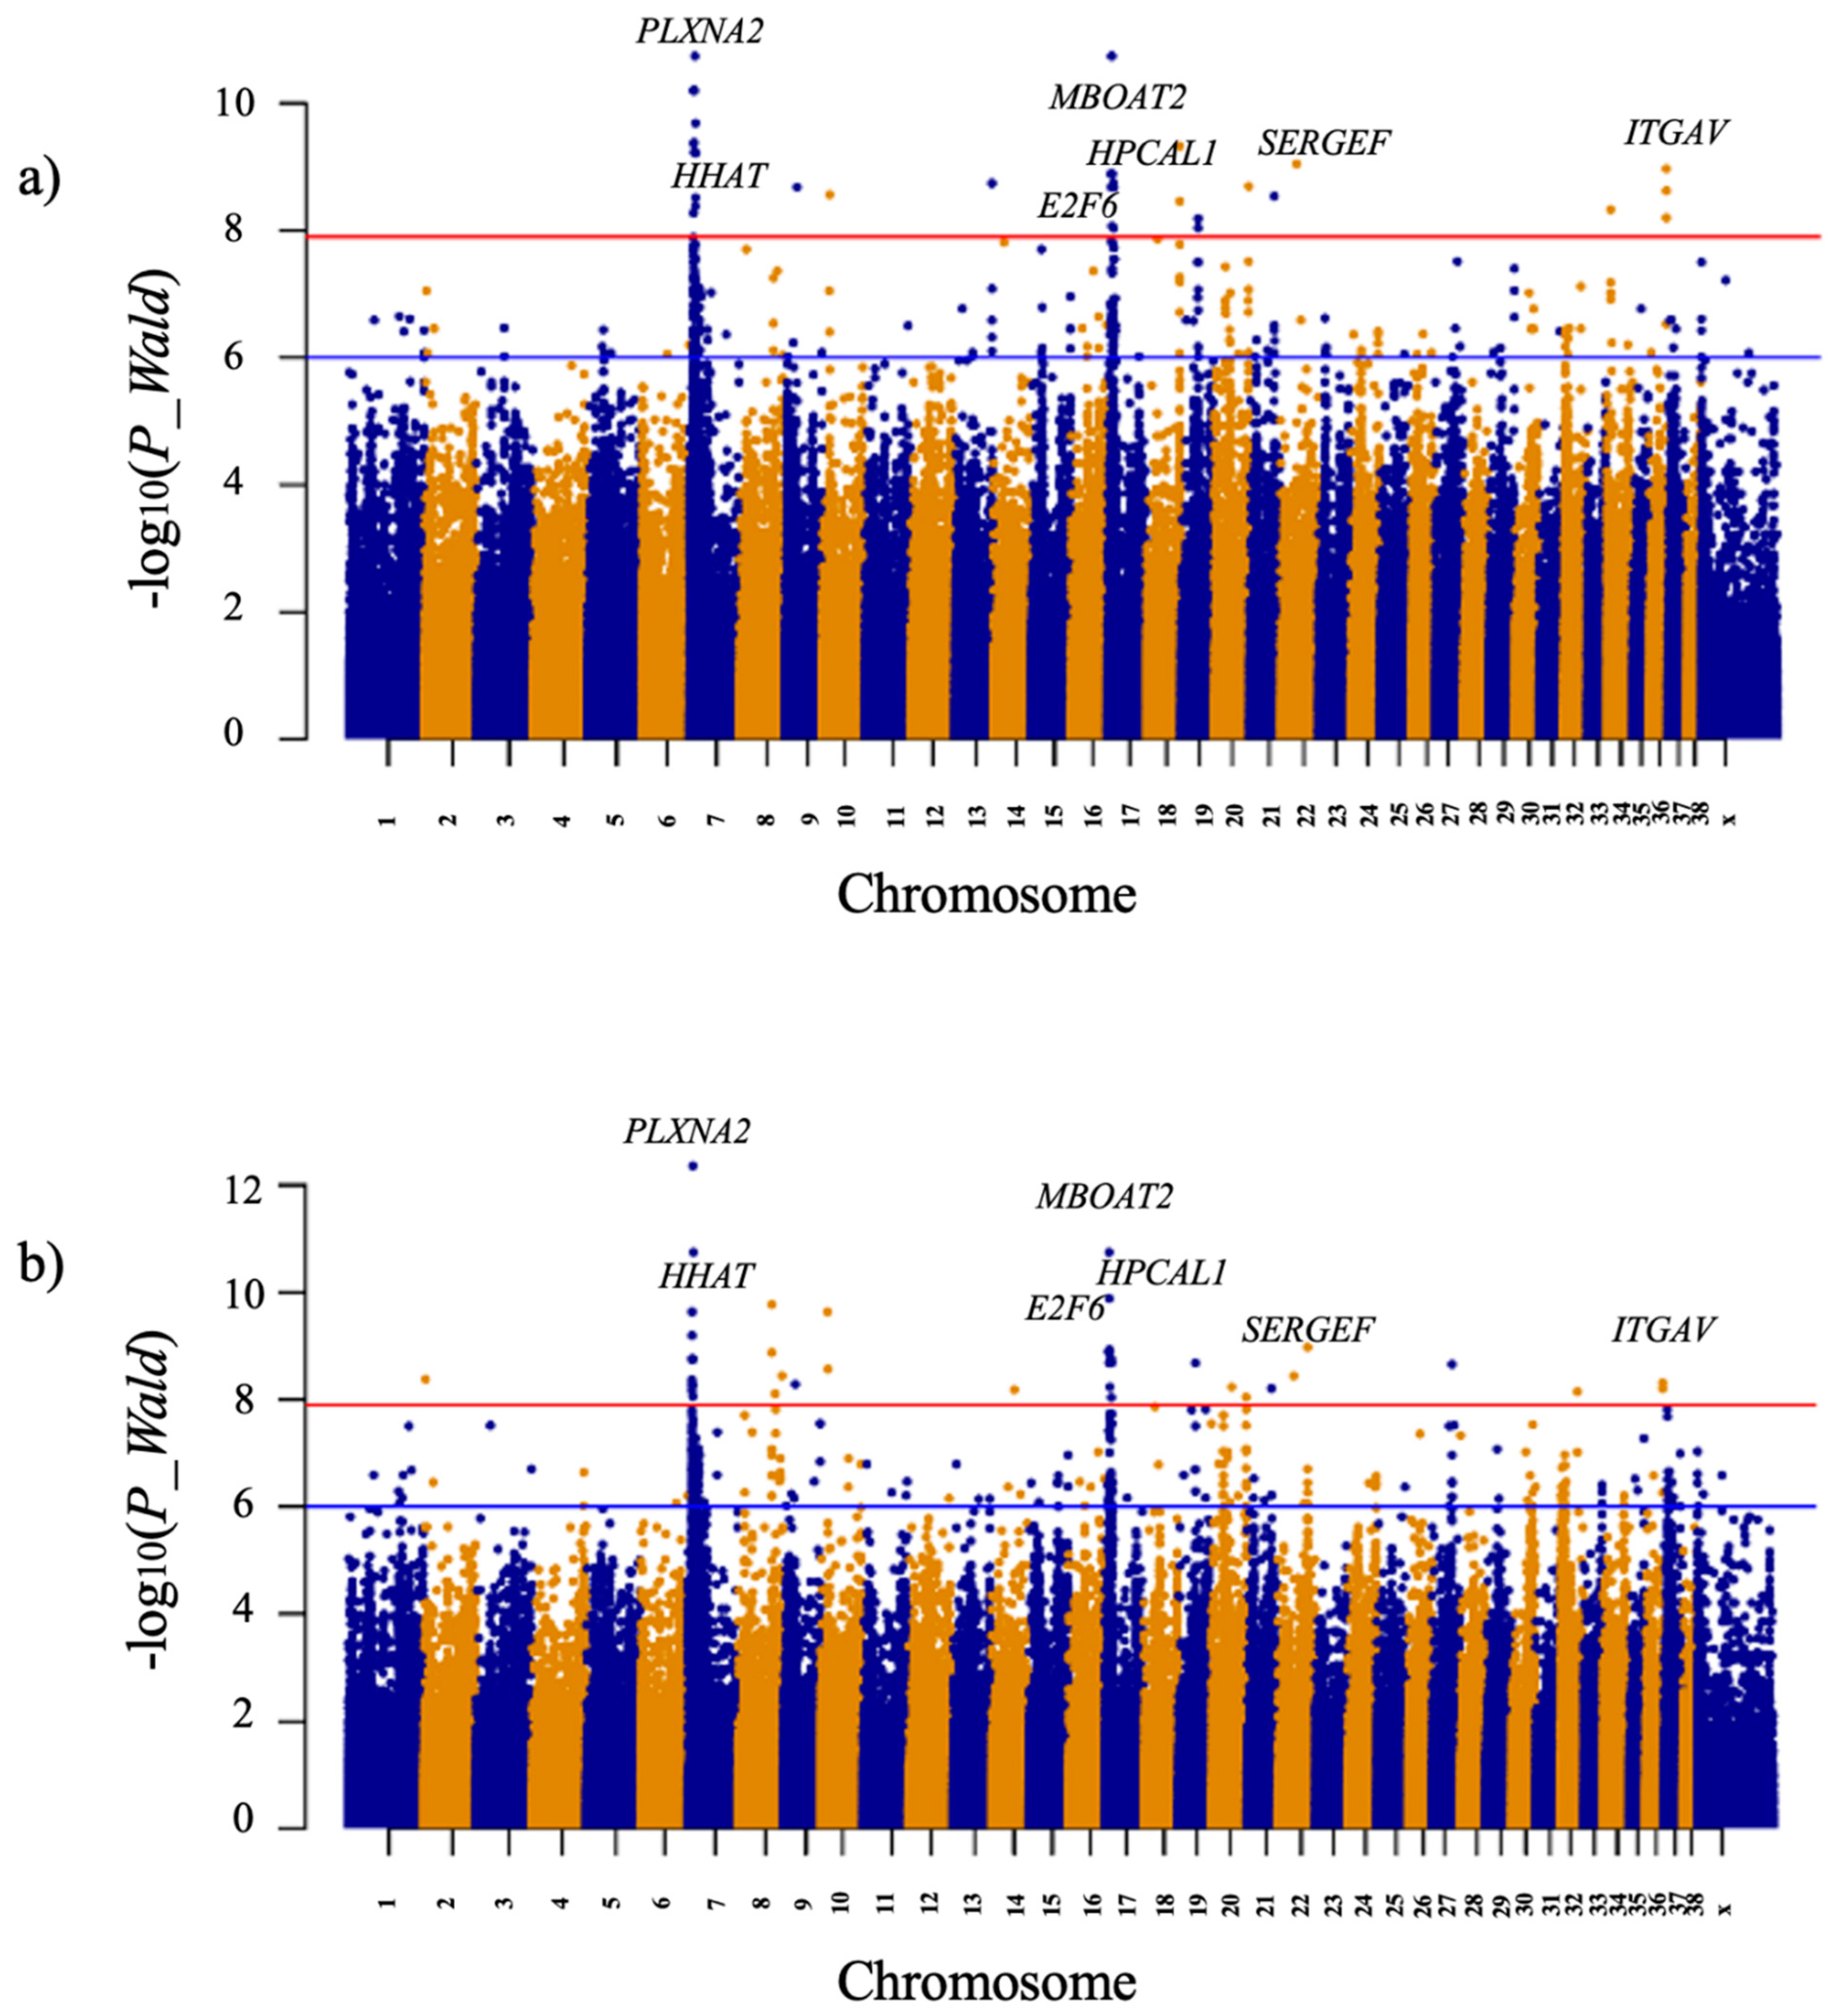

3. Results

| Position/Region in Canfam 3.1 Assembly | Gene Name and Symbol | Candidate Variants | |||

| CFA7:6938927-7043294 | plexin A2 (PLXNA2) | T/C | 7043294 | 6.23 × 10−11 | Intronic/Branch Site mutation |

| CFA7:9012453 | hedgehog acyltransferase (HHAT) | InsT | 9012453 | 1.80 × 10−11 | Intronic |

| CFA17:6251280 | membrane bound O-acyltransferase domain containing 2 (MBOAT2) | G/A | 6251280 | 1.28 × 10−9 | Upstream 5′UTR |

| CFA17:7242110 | hippocalcin like 1 (HPCAL1) | C/T | 7242110 | 1.80 × 10−11 | Upstream 5′UTR |

| CFA17:8153564 | E2F transcription factor 6 (E2F6) | A/G | 8153564 | 1.28 × 10−9 | Downstream 3′UTR |

| CFA21:40329686 | secretion regulating guanine nucleotide exchange factor (SERGEF) | C/A | 40329686 | 2.88 × 10−9 | Intronic/Branch Site mutation |

| CFA36:28842415-28868657 | integrin subunit alpha V (ITGAV) | A/G | 28842415 | 6.29 × 10−9 | Intronic |